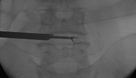

Im Zentrum für Wirbelsäulenchirurgie und Schmerztherapie wird das gesamte Behandlungsspektrum bei Erkrankungen, Unfällen und Schmerzsyndromen der Hals-, Brust- und Lendenwirbelsäule sowie der angrenzenden Strukturen bei Kindern und Erwachsenen in interdisziplinärer Vorgehensweise abgedeckt. Rund um die Uhr besteht die Möglichkeit der Maximalversorgung. Häufig erfolgt die Therapie nach einem Stufenschema, bei dem versucht wird, mit weniger eingreifenden Maßnahmen zu beginnen. Je eingreifender die Therapie, umso höher ein theoretisches Risiko des Auftretens negativer Nebeneffekte.

Insgesamt steht die Behandlung von Verschleißerkrankungen im Vordergrund. Des Weiteren werden im Zentrum jegliche Arten von z. B. Unfällen, Infektionen, Tumoren und Metastasen, Deformitäten, rheumatischen und angeborenen Erkrankungen bei Erwachsenen und Kindern behandelt. Jährlich erfolgen neben den konservativen mehr als 15.000 interventionelle Maßnahmen sowie mehr als 3.000 Operationen. Wenn möglich werden minimalinvasive oder bewegungserhaltende Verfahren angewendet.